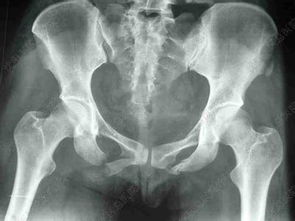

3脊柱骨折一般以壓縮性骨折居多,一般超過(guò)1/3最好就要做手術(shù),不然以后容易腰痛,這個(gè)是個(gè)人可以考慮利弊的,脊柱橫突和棘突的骨折一般無(wú)需特殊處理,壓迫脊髓的骨折都是需要手術(shù)治療的,藥物上我們一般給予甲潑尼龍沖擊治療,防止脊髓水腫不然隨著脊髓腫脹會(huì)造成截癱,粉碎性的骨折如果不是特別嚴(yán)重,并且沒(méi)有神經(jīng)系統(tǒng)癥狀是可以采取保守治療的,但是恢復(fù)的時(shí)間要比較長(zhǎng),股骨頭骨折和粗隆間骨折、股骨干骨折也是要采取切開(kāi)手術(shù)固定,術(shù)前可以進(jìn)行牽引,方便術(shù)中復(fù)位。